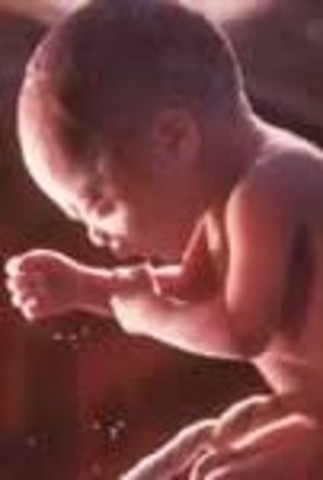

• Week 34: Rapid Growth Continues

Baby is now 18 inches long and weighs 5.25 pounds, child now has excellent chance of survival outside of whom, fat accumulation plumps up the arms and legs this week, eyes open when awake and close when asleep, fingernails are now completely formed